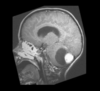

Multiple Sclerosis

Periventricular plaques